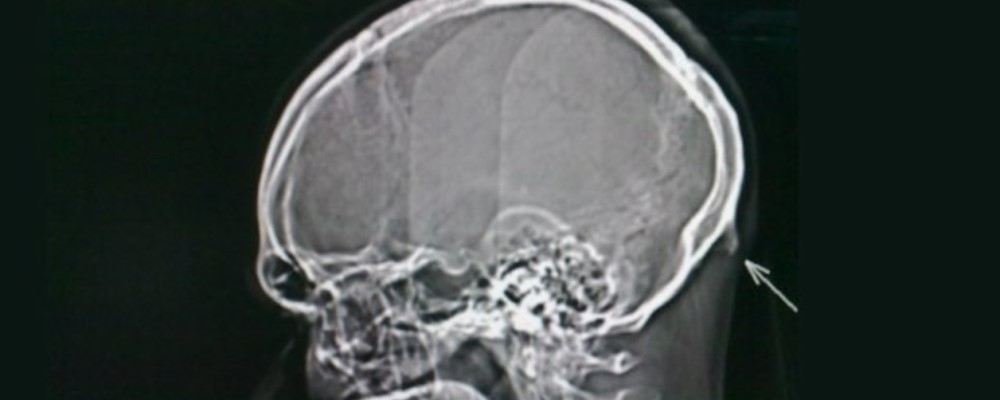

Según la Universidad de Sunshine Coast, el estudio involucró 2018 rayos X de personas entre 18 a 30 años en la costa de Australia, encontrando que el 41% desarrolló un hueso detrás del cráneo de unos 10 a 30 milimetros.

El Doctor David Shahar comentó que el hueso era exclusivo en pacientes de mayor edad, por lo que es increíble que esté pasando en personas jóvenes. «Es importante entender que en la mayoría de los casos, el hueso se desarrolla unos pocos milímetros, pero las proyecciones indicaron que ya existen huesos entre 10 a 30 milimetros en la población joven», comentó.